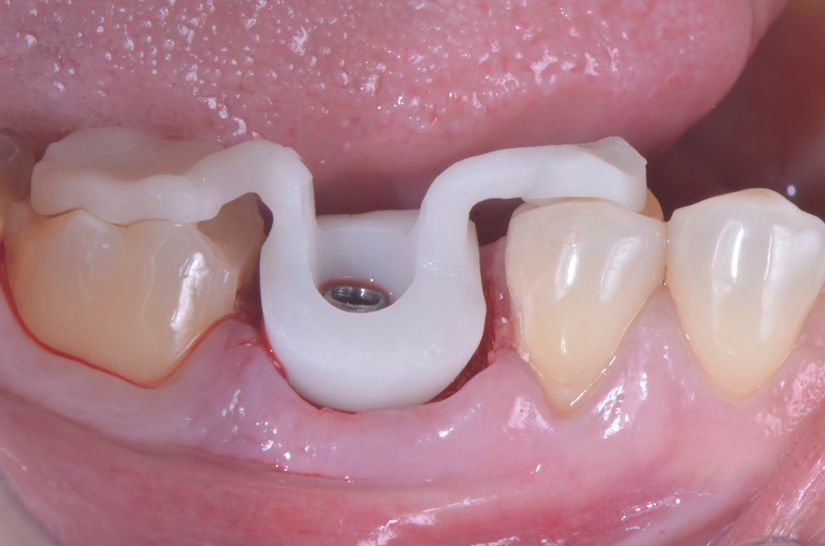

O paciente apresentou fratura vertical mésio-distal no elemento 46. Foi planejada a exodontia minimamente traumática e instalação imediata do implante Maestro Superiore (Implacil Osstem) utilizando uma guia prototipada. Após a exodontia, o implante foi instalado seguindo o protocolo de cirurgia guiada. O GAP vestibular foi preenchido com o Extra Graft. Um cicatrizador personalizado impresso com haletas facilitadoras foi capturado com resina flow e instalado. Após 30 dias, foi realizado escaneamento indireto para obtenção do perfil de emergência, utilizando protocolo digital com sobreposição do cicatrizador escaneado para confecção da coroa definitiva em zircônia policristalina estabilizada por ítria.

O uso de cicatrizadores personalizados, especialmente confeccionados por impressão 3D, tem ganhado destaque por permitir a conformação tecidual progressiva, facilitando a reprodução do perfil de emergência no fluxo digital6,7. A captura do cicatrizador com haletas de retenção com resina flow e seu posterior escaneamento são etapas críticas para assegurar a fidelidade da transferência do perfil de emergência e garantir um planejamento restaurador mais previsível8.